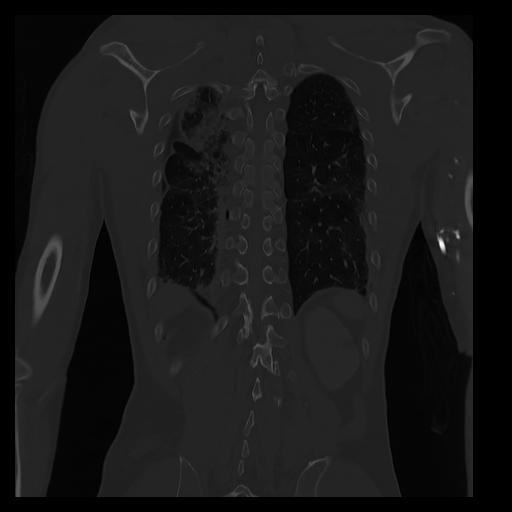

32 PULMON,CE,Coronal,3.000,PULMON,Coronal,